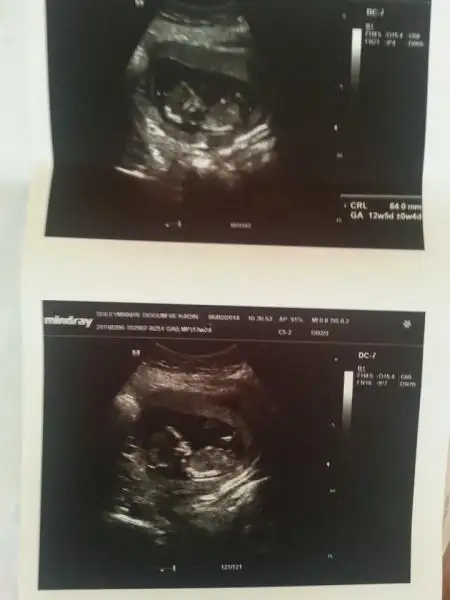

dr soylemeden siz gorun genital nub teorisi ( bebegin cinsiyeti)

Zeynebimm defneee cinsiyet beli oldu tahminleriniz doru ciktii

Iki kizimdan sonra birde oglum olacakmis allahin izniyle..